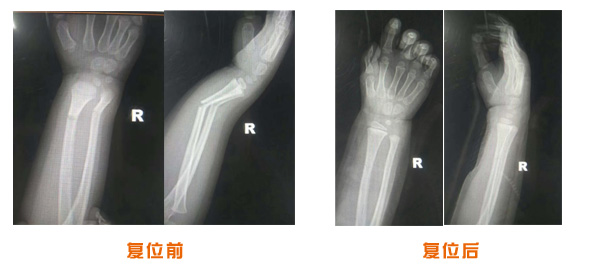

復位前后對比

肘關節脫位骨折治療前后對比